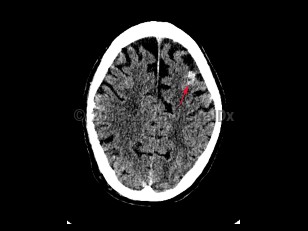

Subarachnoid hemorrhageSubarachnoid hemorrhage